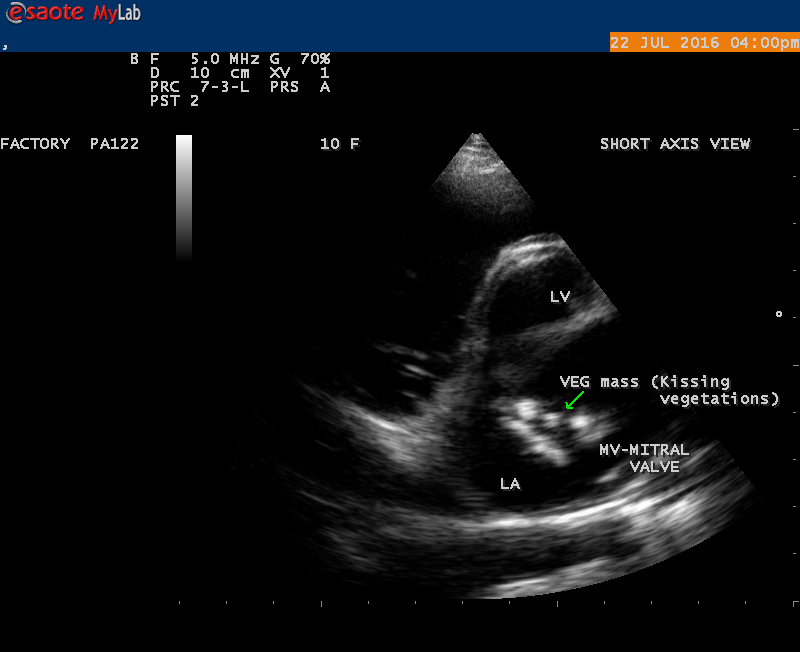

A 10 year female child was referred for echocardiographic evaluation with an apical systolic murmur. The child was having recurrent episodes of rheumatic fever (febrile illness with joint pains) at the age of 5-6 years and taken some treatment from the local medical practitioner, but she was not taken penicillin prophylaxis earlier. The child was remained afebrile for long period and no precipitating factors of infective endocarditis such as dental or genitourinary procedures in the past. General examination revealed normal growth and development, no cyanosis and clubbing and peripheral signs of infective endocarditis such s Osler’s nodes, Janeway lesions, Roths spots and splinter haemorrhages are not present and they are relatively rare in children. Physical examination revealed a grade 3/6 , blowing, high pitched, holosystolic murmur with a constant intensity and duration on dynamic auscultation and loudest at the apex with a radiation to left axilla and transmitted to the left infrascapular area and vertebral coloumn and it is due to the flow generating the murmur is directed posterolaterally within the left atrial cavity, suggesting the murmur of mitral regurgitation due to the rupture of chordae tendineae of anterior mitral leaflet. Blood culture revealed normal. Blood chemistry revealed the positive serum ASO titer, suggesting a recent streptococcal infection and other parameters are normal. X- ray chest reveled moderate cardiomegaly and ECG revealed a left ventricular volume overload pattern of eccentric hypertrophy due to LV dilatation as a result of severe mitral regurgitation and a normal rhythm. Transthoracic echocardiography revealed a giant vegetation ‘popcorn’ like in Figures 1,3 and 4 and ‘cucumber’ like in Figure 2, mainly attached to base and apical portion of anterior mitral leaflet as shown in Figure 31 and manifested in various size and shapes as shown in Figures 1 to 33. A flail anterior leaflet with a disorganized mitral regurgitation jet as shown in Figure 16 and 21 and the posterior leaflet is embedded with vegetation and resulting in ‘kissing forms’ as shown in Figures 13, 14 and 15 in echocardiography imaging. Tricuspid valve is also thickened and calcified as shown in Figure 2 in addition to thickened and calcified mitral leaflets, suggesting an underlying rheumatic etiology predisposing to the formation of vegetation. The child was given 1.2 million units of intramuscular benzathine penicillin injection as a therapeutic and initial prophylaxis dose for rheumatic fever and advised every 3 weeks for life long. Small doses of digoxin and diuretics are also prescribed and advised early surgery (mitral valve replacement) Transthoracic 2D images are as in Figures 1 to 33 are given below

The most common and direct evidence of infective endocarditis is the vegetation and it begins as a microscopic focus of infection and gradually grows into a conspicuous mass. It is typically an irregularly shaped, highly mobile, echogenic mass attached to the free edge of a valve leaflet ( most commonly at the coaptation line) and tends to develop on the ‘upstream’ side of the valve leaflets ( ie, the ventricular side of aortic valve and the atrial side of mitral and tricuspid valves. They may be seesile or pedunculated, but usually has an oscillating or fluttering motion, a typical feature of most vegetations. Vegetation move with the leaflet in a more chaotic (‘oscillating’) manner and it may prolapse through the valve into the LV (left ventricle) as it opens as shown in Figures 3, 4 and 16 and into LA (left atrium) as it closing (Figure 5 and 6) . The mass of vegetation is typically homogeneous with echogenicity similar to that of the myocardium. The infectious process often alter the valvular structure and function. Extensive involvement of the leaflet may result in chordal rupture, leading to severe regurgitation as shown in Figure 21 . Direct and typical signs of RMCT (ruptured mitral chordate tendineae) were chain-flail or whiplash-like changes and had an incidence of 86.7%, causing severe regurgitation and mitral chordal rupture is the leading cause of flail mitral leaflet[30]. A large vegetation may obstruct the valve orifice as shown in Figure 1 and 2 , sometimes termed as “obstructive-type bacterial endocarditis” and producing a functional valve stenosis ( Ping-Pong mitral stenosis [31]) similar to left atrial myxoma as shown in Figure 29.

The shape of vegetation varies in this child as ‘popcorn’ like (Figures 1,3 and 4 ), rod-shaped (Figure ), basket shaped (Figure 7 )[33-Figure 13.3], ‘baby in hand’ appearance (Figure 18), ‘cucumber shaped (Figure 2 ) and a ‘bunch of plantain’appearance (Figure 33 ), ring shaped (Figure 19 }, bileaflet structure (Figure 9 )with bileaflet MR jet as shown in Figure 10 . and kissing forms (Figure 13 - parasternal long axis view, Figure 14 - apical four chamber view and Figure 15 - short axis view)